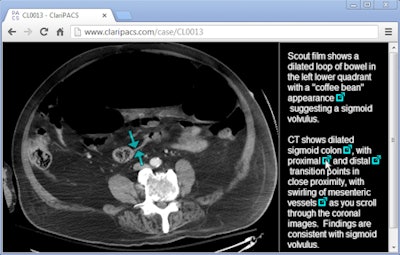

![]() |

| Interactive radiology report in ClariPACS allows linking of annotated key images. The entire study and interactive report can be emailed to a colleague. Image courtesy of Dr. Ed Boas. |